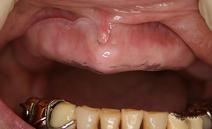

保湿装置(モイスチャープレート、モイスチャートレー)

ドライマウス治療の基本は「口腔の保湿」で、乾燥状態がひどい、あるいは睡眠中に口が乾くという人には、保湿装置が有効です。これは歯ぎしり防止用のナイトガードと類似した形状で、保水スペースに水で湿らせたガーゼやスポンジ、保湿剤などを入れた状態で、上顎に装着して使用します。また、ハード型とソフト型があり、使用感や好みによって使い分けることができます。歯科でご相談ください。

![]() 歯がない場合も作成可能 |